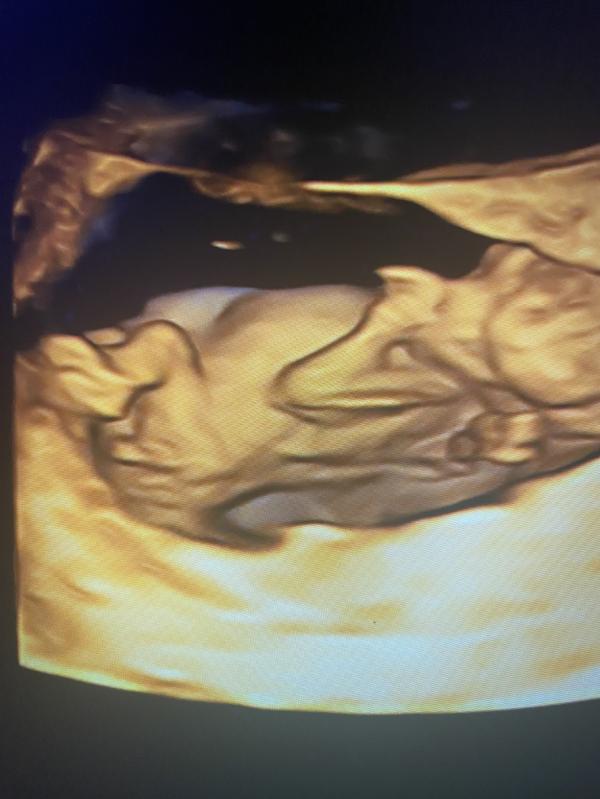

2-ой скрининг.

Слава Богу, всё в порядке.

Девочки, через неделю скрининг, где узнаем пол малыша. Предлагаю пока погадать, кто у нас) сделала фото с видео, где видно бугорок. Сама я в этом не бум-бум.